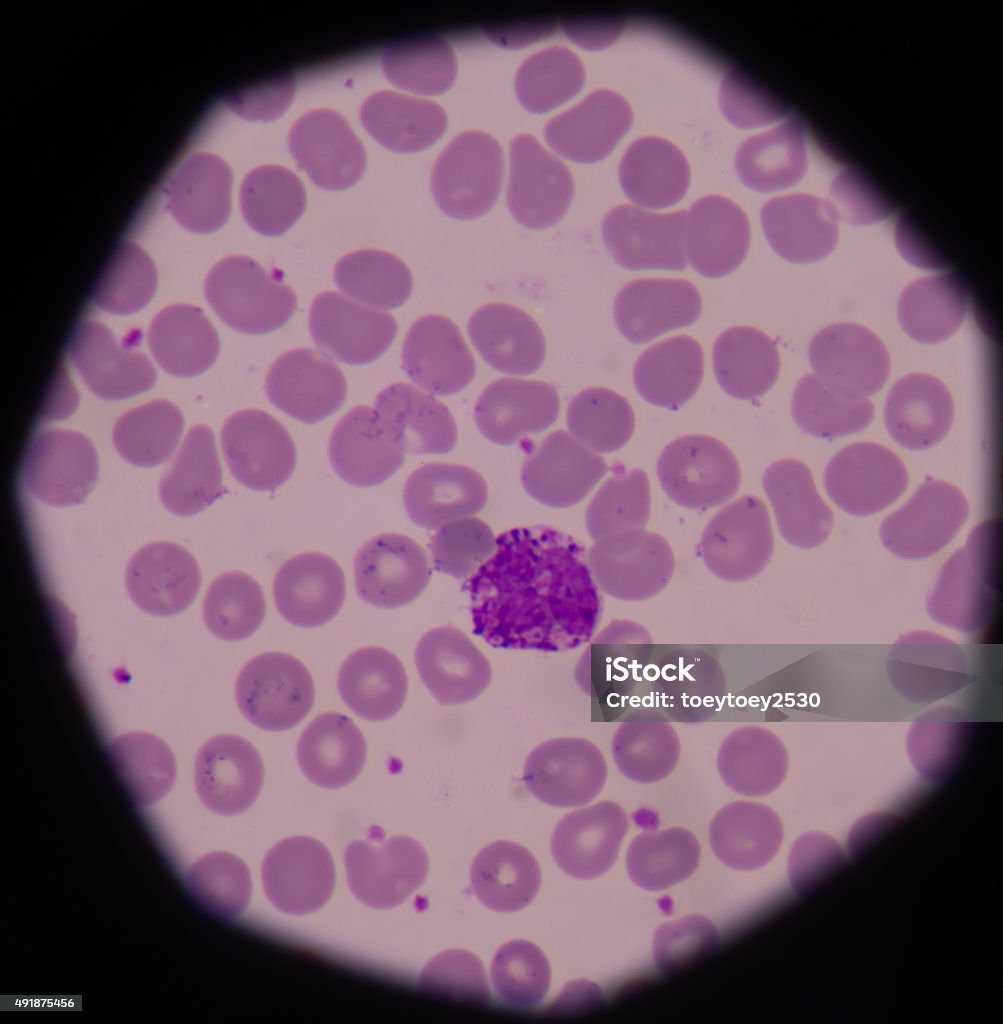

Структура клеток: Эктоплазма и цитоплазма в научных изображениях

Раздел: Галерея прозрений